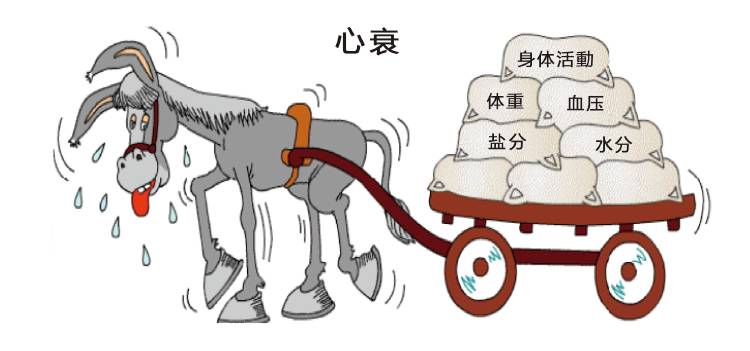

一、心衰是什么?

你知道什么是心衰吗?

♥2.心力衰竭是心血管病发展到了严重的阶段,心脏的泵血功能衰退,就像弹性减退的“皮球”,输出血量不能够满足身体代谢的需要,器官和组织中的血液也不能顺利回流到心脏,这种状态就叫做心力衰竭。